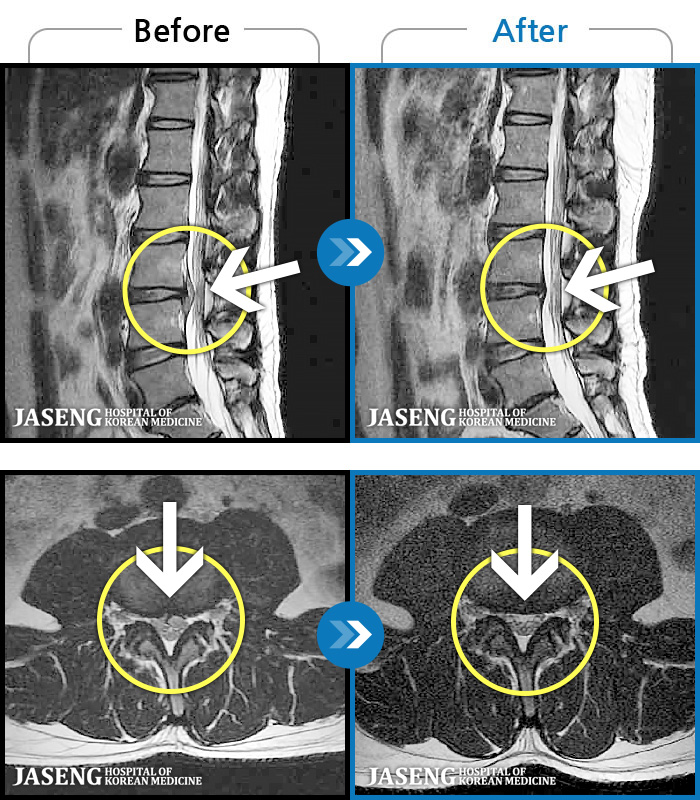

MRI ġ

119 MRI ũ ʸ Ȯϼ.

[Կñ:22.08.30~24.08.05]

[_㸮ũ] ٸ ߳ .

No.118

ȸ 516

2024.12.24